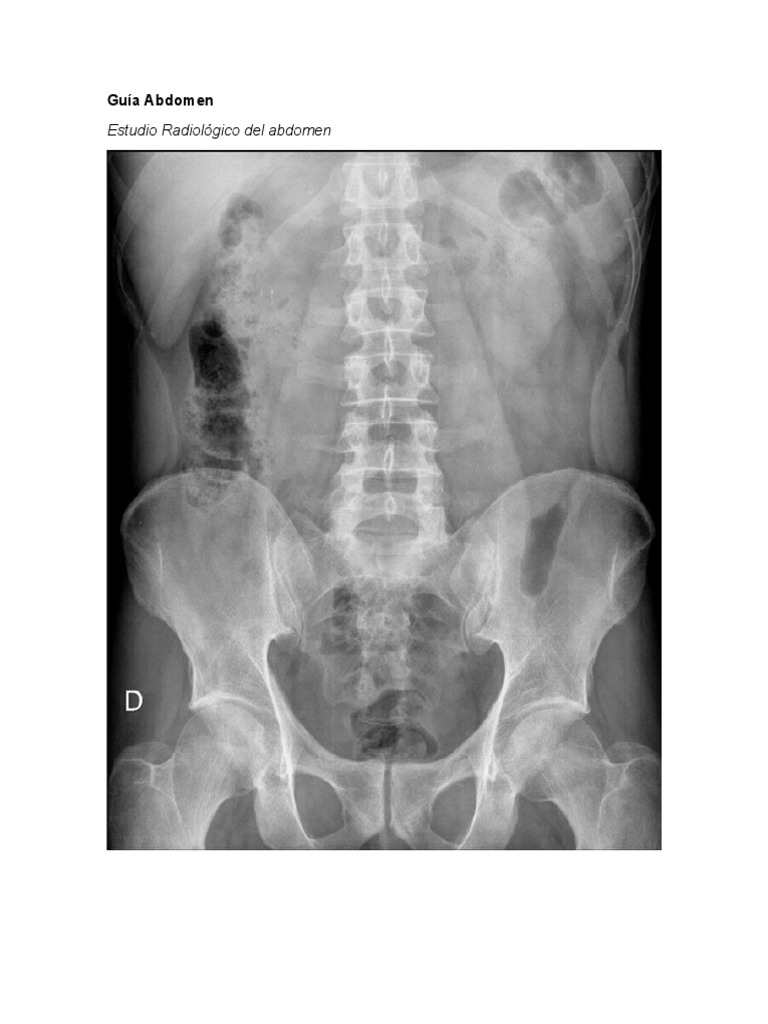

Guía Abdomen

Estudio Radiológico del abdomen

-Proyección básica: radiografía en decúbito supino

La radiografía de abdomen no requiere ningún tipo de preparación previa por parte

del paciente y suele realizarse en posición decúbito supino o en alguna otra

posición si el especialista así lo indica (Imagen 3). Para su realización será

necesario desnudarse y desprenderse de cualquier objeto que se puede tener,

especialmente joyas y objetos metálicos. La exposición a radiación ionizante por

parte del paciente como consecuencia de esta prueba diagnóstica, es leve y no

supone un riesgo importante para su salud.